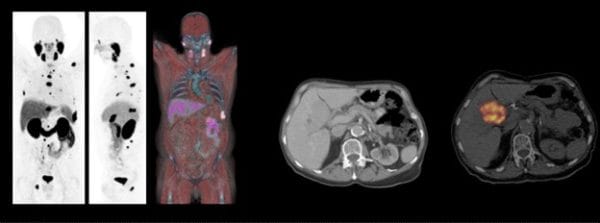

ONCOLOGY, expand capabilities beyond traditional PET/CT imaging with Biograph mCT. Designed to support low-dose and fast imaging, biograph mCT enables a comprehensive oncology imaging workflow. Dedicated technologies, such as deviceless gating, whole-body dynamic imaging, and RT planning packages reveal critical details while ensuring patient comfort and care.

All photographs and data are a courtesy of Siemens Healthcare GmbH.